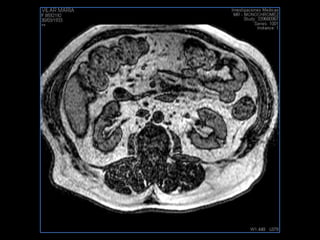

PROTOCOLO pancreas/ riñon AXIAL fat sat /AX in phase out phase AX T1 +SAG T2  COR T2, CON   GADOLINIO :  COR T1+AX T1(DIN) SAT: NO  FASE: RL THK: 4MM  COIL:  GAP: (FACTOR 1.4) 1MM FOV: 40 CM NEX:2 SINCRONIZACION RESPIRATORIA EN 3 O 4 CICLOS ALE

resonancia de abdomen